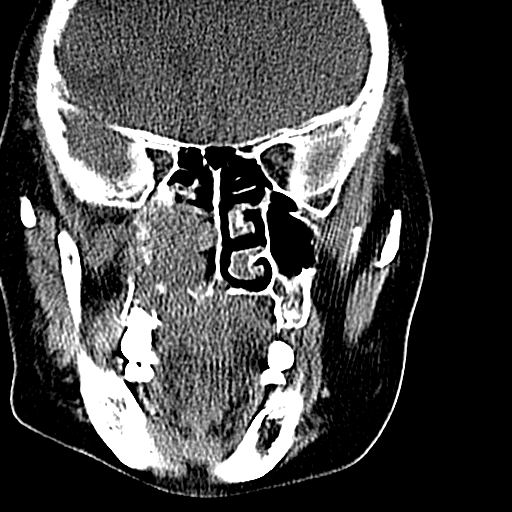

标题: CT19708:单侧上颌窦病变

老年患者,女。鼻塞多年。

考虑右侧上颌窦良性占位性病变,粘液囊肿可能性大;建议活检。

膨胀性生长,且骨质无破坏,说明时间久,良性;从密度,边缘看,内部还见坏死区,应该是实性肿瘤,定性,影像学无绝对的特异性

病灶密度很不均匀,骨壁膨胀中有断裂,考虑内翻乳头状瘤可能性大,粘液囊肿不排除

膨胀性生长,且骨质无破坏,说明时间久,良性;从密度,边缘看,内部还见坏死区,应该是实性肿瘤,定性,影像学无绝对的特异性,考虑内翻性乳头状瘤可能